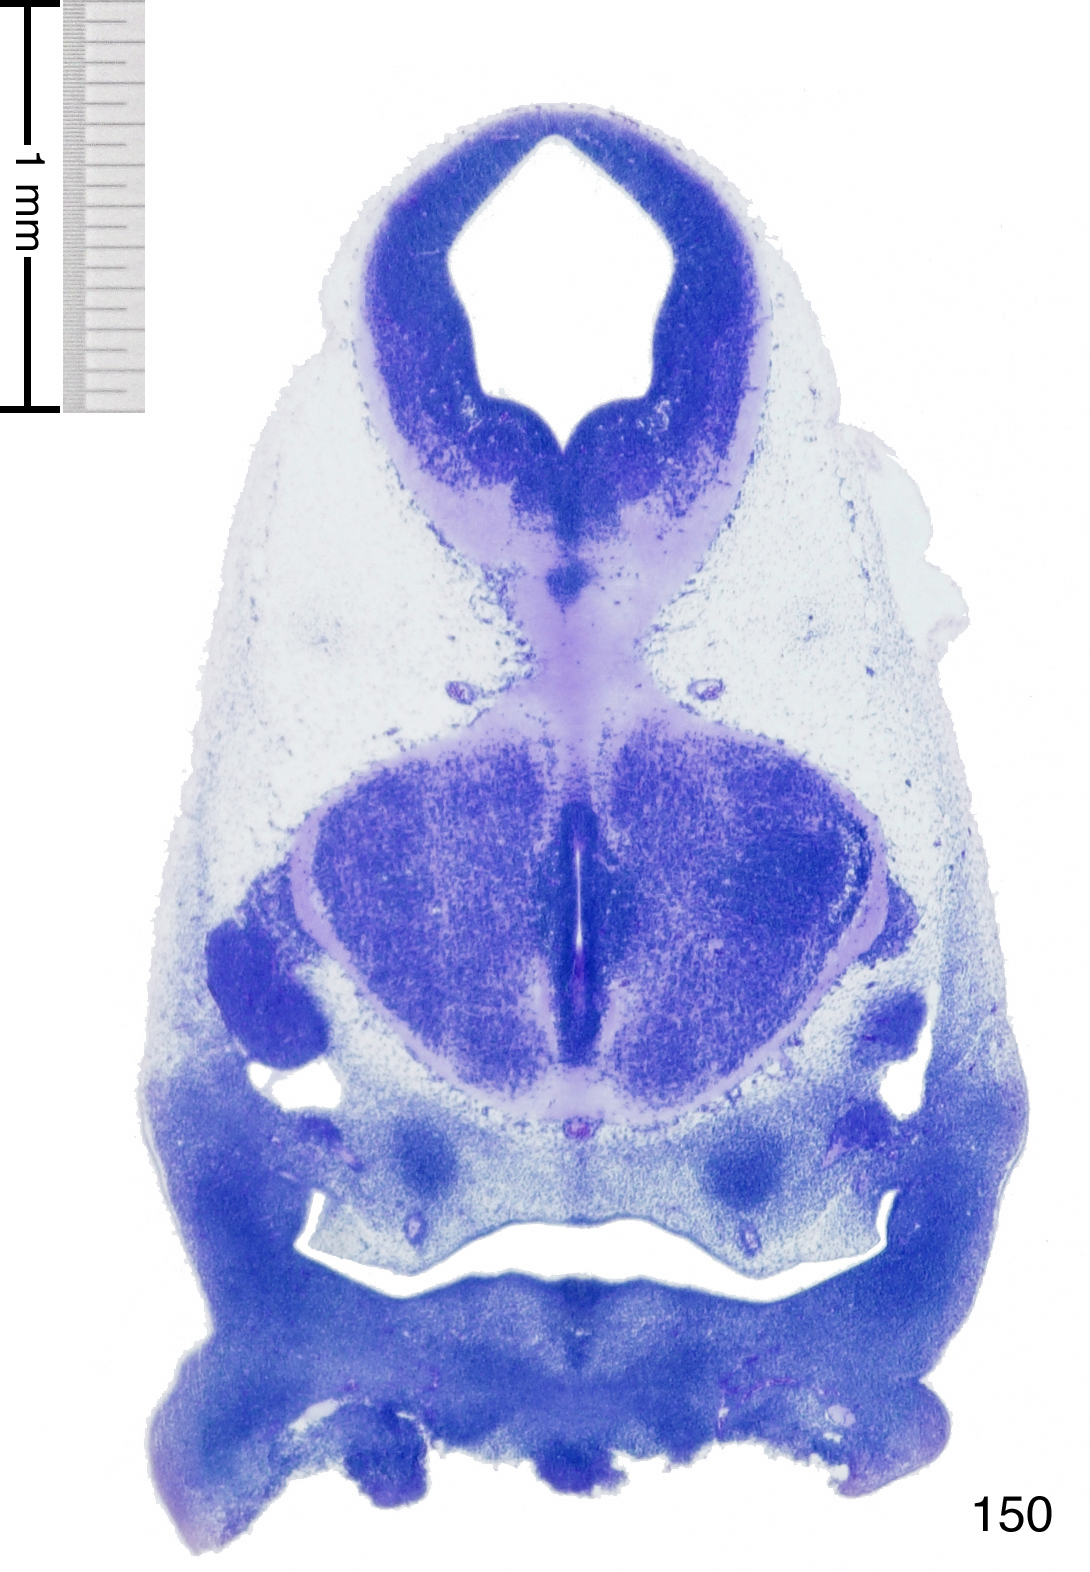

C57BL/6J GD12 Mouse Brain Atlas

Slides from U. Schambra, coronal cuts with slides at every 5th section, with a hematoxylin and eosin (H & E) stain

Currently on section 150.